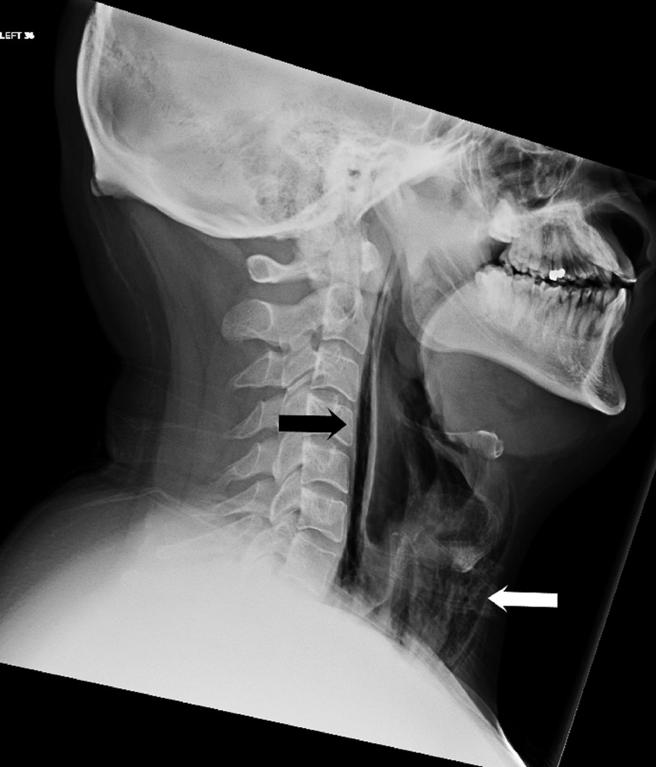

La radiografia a raggi infrarossi della zona retrofaringea. Credit: British Medical Journal

L’uomo aveva la faringe spaccata e un buco nella zona in cui questa si collega con l’esofago, il suo corpo presentava inoltre delle bolle d’aria tra il tessuto della pelle.

Quando il ragazzo arrivò in ospedale fu immediatamente visitato e fu notata una profonda fessura al torace.

A causa della rottura della faringe, il paziente rimase in ospedale per diversi giorni, nutrendosi attraverso un tubo.